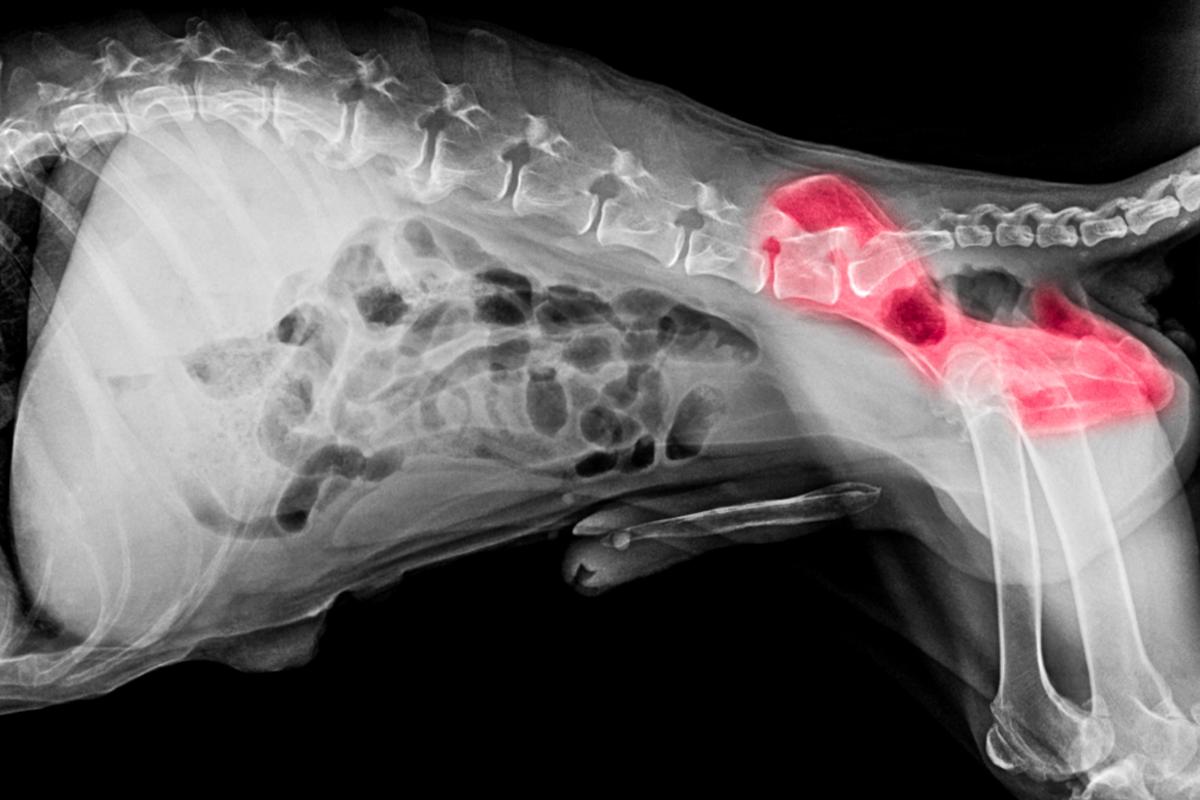

Displasias

La displasia de cadera y la displasia de codo son patologías degenerativas y hereditarias de tipo osteoarticular que suelen afectar a perros de razas grandes y gigantes. Cuando la displasia es avanzada, provoca problemas notables de movilidad y cojeras persistentes, pero en estadios iniciales, puede ocasionar unas cojeras más leves y de tipo intermitente. Así pues, es posible que un perro con displasia corra y juegue sin que seamos capaces de percibir de manera evidente una cojera pero esta se hace más clara cuando el animal camina o realiza algún tipo de movimiento específico.

Además, en el caso de la displasia de cadera, los animales, sobre todo aquellos más jóvenes, suelen mantener sus patas traseras juntas cuando saltan, por lo que parece que den "saltos de conejo" y tienen una peculiar forma de sentarse y tumbarse, lo que puede dar señales de que algo no va bien.

La displasia puede controlarse a través de tratamientos y, en ciertos casos, se puede llegar a corregir con cirugía.